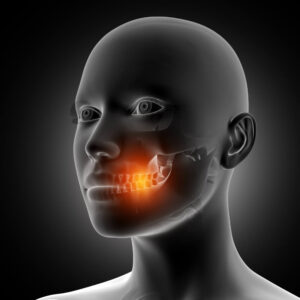

Teeth are made up of different layers — enamel, dentin, pulp, and cementum. Enamel, which is the hardest substance in the body, is on the outside of the tooth. The second layer is dentin, which is softer than enamel, and the deepest layer inside the tooth is pulp, which consists of nerves and blood vessels. Cementum is on the root of the tooth and is beneath the gums.